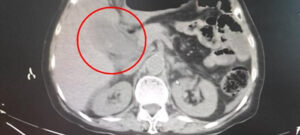

95 viên sỏi túi mật: Bác sĩ cảnh báo nguy hiểm từ thói quen ăn sáng bỏ bữa

Sốc khi lấy ra 95 viên sỏi từ cơ thể người phụ nữ 40 tuổi...